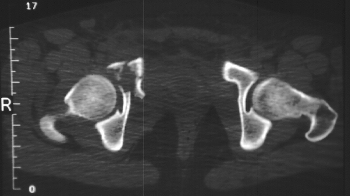

Radiographs:

Radiographs revealed a vertical buckle fracture of the right inferior sacrum, oblique fractures of the superior and inferior rami on the right and a fracture through the medial acetabulum. Obturator and iliac oblique inlet and outlet pelvic views, and a thin cut CT with 3-D reconstruction of the acetabulum were performed. These elucidated a comminuted anterior wall with fracture line extending to the posterior column. The posterior column was non-displaced. The pelvic fracture was non-displaced.

Assessment:

1. Right T-shaped acetabular fracture with anterior wall comminution.